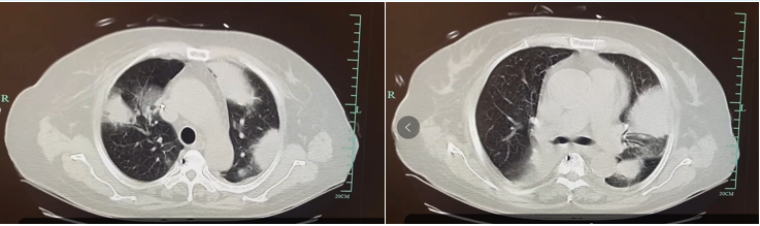

影像学资料

ICU前2天CT显示两肺多发团块、高密度影,入ICU当天CT示病变进展。

入ICU前2天胸部CT

入ICU当天胸部CT

4为本例患者入ICU时的影像学表现,磨玻璃影中混杂边缘相对清晰的实变影为主。

图片

4  本例患者入ICU影像学表现

左氧氟沙星治疗5天,期间痰培养提示念珠菌(+)仍有高热,Tmax 38.8℃;WBC 1.8×109/L,PCT 0.34 ng/mlCRP 113 mg/L氧合指数195 mmHg去甲肾上腺素间断维持血压复查肺部CT:团块、高密度影较前并未减小,实变加重。

复查胸部CT

患者临床症状改善欠佳,影像学进展。原因考虑:军团菌治疗效果欠佳?合并其他病原体感染?胞内病原体治疗效果滞后?肺水肿?

联合治疗疗程2周,患者无发热,呼吸机间断脱机,循环稳定复查肺部CT:团块影基本消失,两下肺余少量实变影。停用阿奇霉素,改口服左氧氟沙星片剂